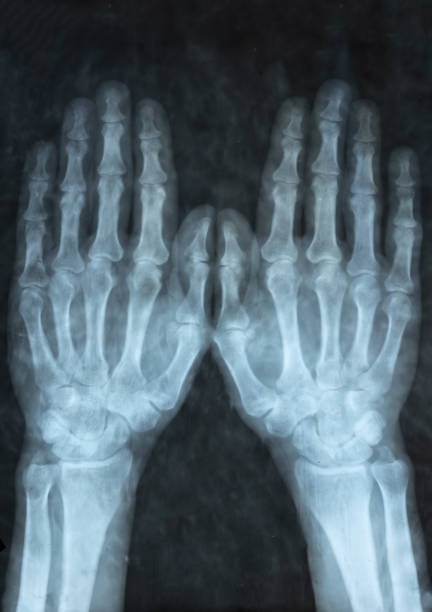

해부학적 이상은 척골충돌증후군의 주요 원인 중 하나로, 팔꿈치와 손목 사이의 뼈 구조나 관절 배열에 선천적 혹은 후천적 변형이 있을 때 발생할 수 있습니다. 예를 들어, 척골이 정상보다 길거나 뼈의 돌출부가 비정상적으로 발달하면 손목과 척골 사이의 공간이 좁아져 충돌이 발생하기 쉽습니다. 이런 구조적 이상은 일상적인 움직임에서도 반복적으로 뼈와 인대, 힘줄 사이에 마찰을 일으켜 염증과 통증을 유발합니다. 해부학적 이상은 개인마다 다르게 나타나며, 증상이 심하면 기능 저하와 만성 통증으로 이어질 수 있습니다. 정확한 진단을 위해 X-ray, MRI 등의 영상 검사가 필요하며, 치료는 보존적 방법부터 수술적 교정까지 다양하게 적용됩니다. 조기에 이상을 발견하고 적절한 관리와 운동으로 관절의 움직임을 개선하는 것이 중요합니다.